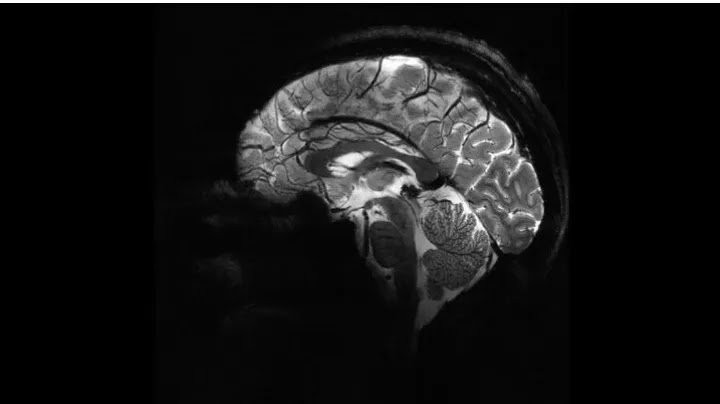

Ερευνητές της Επιτροπή Ατομικής Ενέργειας της Γαλλίας (CEA), σκάναραν για πρώτη φορά έναν ανθρώπινο εγκέφαλο με τον πιο ισχυρό μαγνητικό τομογράφο που διαθέτει σήμερα η ανθρωπότητα.

Περίπου 20 εθελοντές, που δεν αντιμετώπιζαν κάποιο πρόβλημα υγείας, μπήκαν στο μηχάνημα, μετά την έγκριση που δόθηκε από τις αρμόδιες υπηρεσίες για τη χρήση της τεχνολογίας σε ανθρώπους.